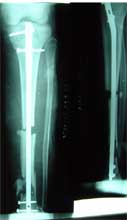

长骨干的力学特点是负重,两端为大关节,附着肌肉力量较大,应力突出。钢板内固定时广泛的软组织剥离,容易损伤血液循环和关节功能。 带锁髓内钉在骨组织和钉体之间提供较均匀的弹性应力分布,避免,抗旋转作用强于可屈髓内钉,不需外固定,对断端稳定性好,可早期功能锻炼。有优于钢板、外固定架和可屈髓钉的特点,已经成为治疗新鲜长骨干骨折的有效方法 。 但在长骨干骺端骨折、骨不连时,由于锁钉距离主钉孔较远,约在1.5-5.5厘米范围内,锁定骨折端有困难。 ZIMMER公司新型的带锁髓内钉可用于治疗长骨干骺端骨折、骨不连。由于锁钉距离主钉孔较近,约在0.5-3.5厘米范围内,可以满意锁定长骨干骺端骨折、骨不连。

采用特殊的带锁髓内钉固定多段骨折,可以采用闭合穿针方法,即不切开骨折部位的软组织,不破坏血液循环,不用外固定,可以早期锻炼关节,关节功能好,骨折愈合快。